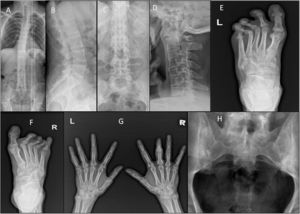

Plain radiographs were obtained of the involved joints according to standardised projections for different joints when clinically indicated in both groups (Fig. 2A–H).

(A & C) Ankylosing spondylitis: X-ray whole spine and thoracolumbar spine AP view showing diffuse syndysmophytic ankylosing giving the Bamboo spine appearance, dagger sign (ossification of interspinous ligament) with bilateral sacroilitis; (B) X-ray of the thoracolumbar spine lateral view showing Romanus lesions (Shiny Corner Sign) due to sclerosis of the vertebral body corners; (D) X-ray cervical spine lateral view showing ossification of the anterior spinal longitudinal ligaments from C3-T1; (E) psoriatic arthritis: X-ray of the left foot AP view with poly-articular erosive arthritis of the lateral 3 MTP joints with subluxation and pencil cup deformity; (F) psoriatic arthritis: X-ray of the right foot AP view showing subluxation of the middle 3 MTP joints with marginal erosions; (G) psoriatic arthritis: X-ray both hands AP view showing sausage shaped right middle finger with erosive arthritis of its PIP joint; (H) ankylosing spondylitis: X-ray of the SIJs AP view showing bilateral and symmetric sacroiliitis with subchondral bony sclerosis on both sides.